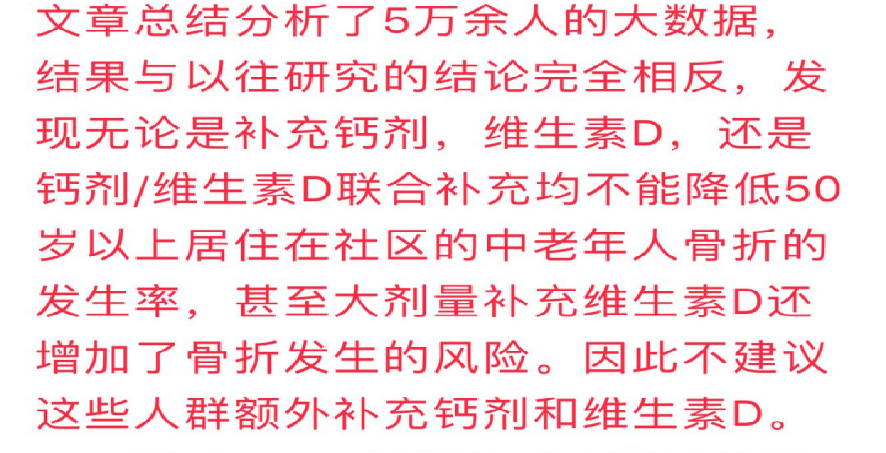

离子钙是个喜欢凑热闹的家伙,又是个比较仗义的好汉。身体里哪个部位有炎症,有战争,离子钙就不会坐视不管,总是见义勇为,挺身而出,为正义两肋插刀。比如肺结核钙化灶就是离子钙帮忙压制住结核病不使病变肆意扩散而砌的“围墙”。

肺结核钙化 肺结核钙化灶